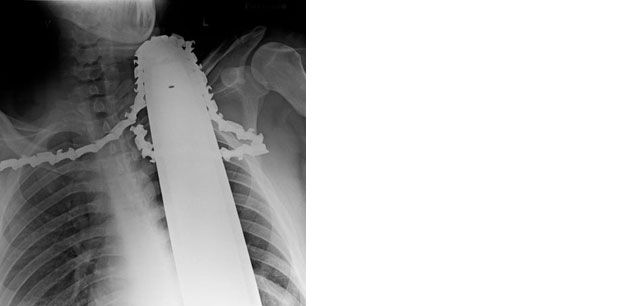

I found the after photo.